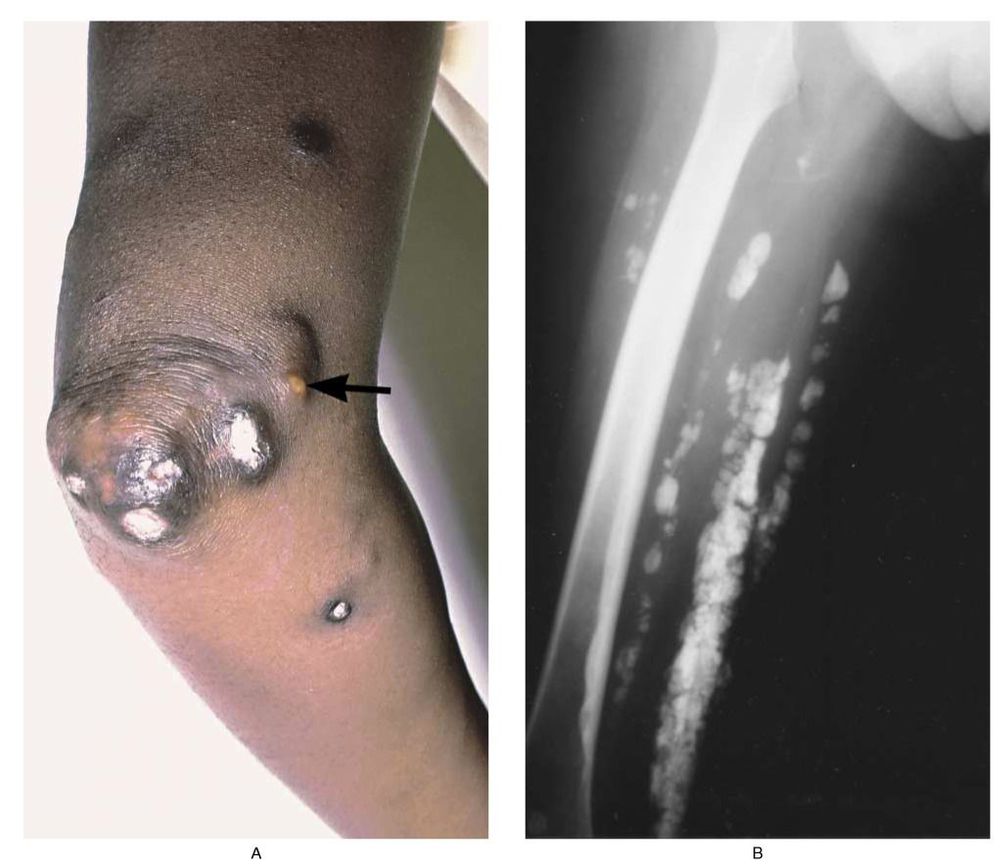

The elbow (Panel A) of a 33-year-old woman who had had dermatomyositis since childhood shows subcutaneous calcifications extruding through the skin. A focus of purulent inflammation within a calcium deposit is evident (arrow). An x-ray film of the patient's thigh (Panel B) shows calcifications beneath the skin and within the muscle tissue. Some lesions on the skin in this area were palpable, and others were not visible. Deposition of calcium continued in this patient despite therapy with prednisone, azathioprine, and diphosphonates. Marinos C. Dalakas, M.D. National Institute of Neurological Disorders and Stroke, Bethesda, MD 20892 source: nejm.org